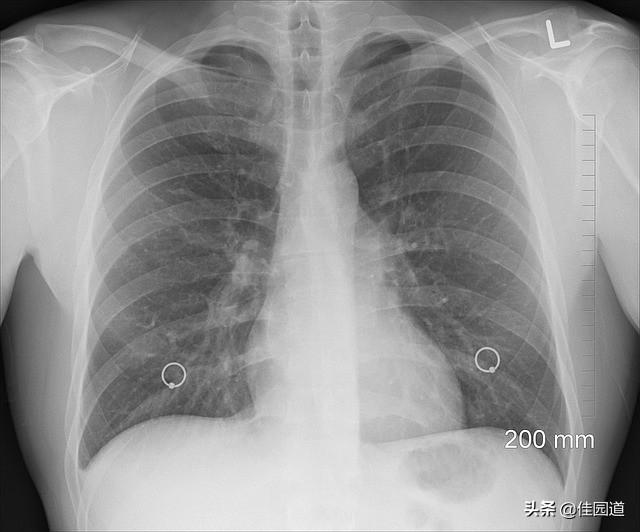

早期肺がん患者の多くは、明らかな自覚症状がなく放置されるため、一般的な肺疾患として盲目的に扱われ、早期発見・早期治療の時期が遅れることが多い。したがって、肺がんを早期に発見するためには、健康診断に注意し、次のような疑わしい症状が現れたら、病院に行って胸部レントゲン写真、胸部CT、喀痰検査、気管支鏡検査などの関連検査を受け、肺がんの除外診断に間に合わせることが必要です。特に、喫煙歴の長い人、放射性物質、アスベスト、ガスに暴露された人、慢性呼吸器疾患や結核に罹患している人は、より注意が必要である。